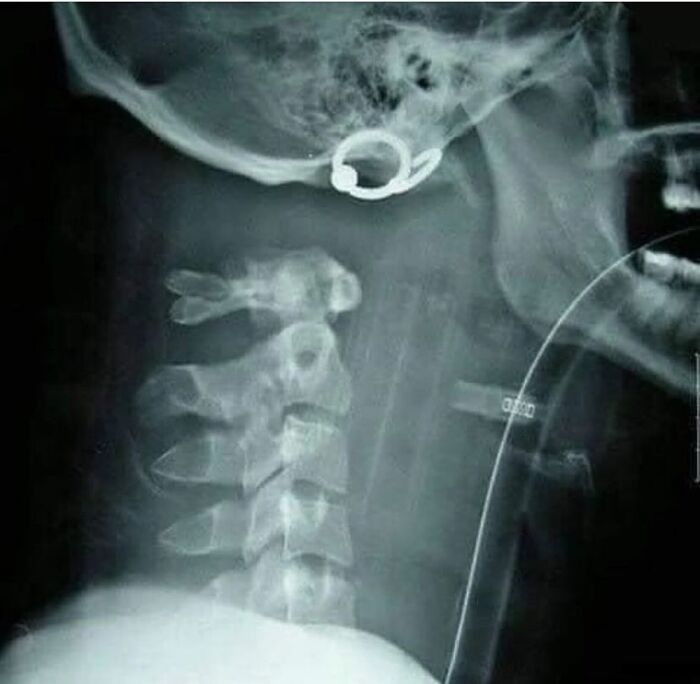

This is called internal decapitation. This person most likely received an impact to the lower jaw resulting in separation of the spine to the skull or was hung by the neck from a height. Internal decapitation is instantaneous death

No. No it's not instant death. There are numerous survivors of it. Usually as a result of a severe car accident. It's not hard to verify facts - why post false ones?